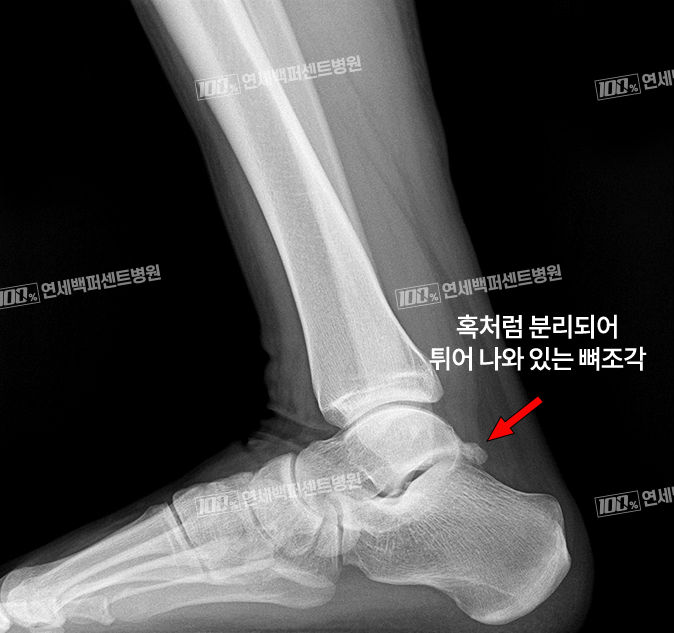

X-ray 소견

후방충돌증후군(삼각골증후군)은 발목뼈 뒤쪽에 분리되어 있는 뼈조각과

그 뒤를 지나가는 힘줄이 충돌하면서 염증이 발생하는 질환!

염증, 충돌을 일으키는 뼈조각만 선택적 제거!